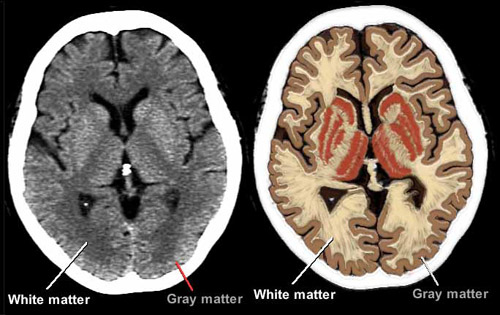

大脑层 - 灰白质

整个大脑是由两层组成。 20毫米厚的最外层,称为大脑皮质(或灰质),包含认知与人格及复杂运动的协调中心。 如将看到的,灰质也被组织为不同的功能。

白质是纤维的网络,使大脑的区域相互连通。